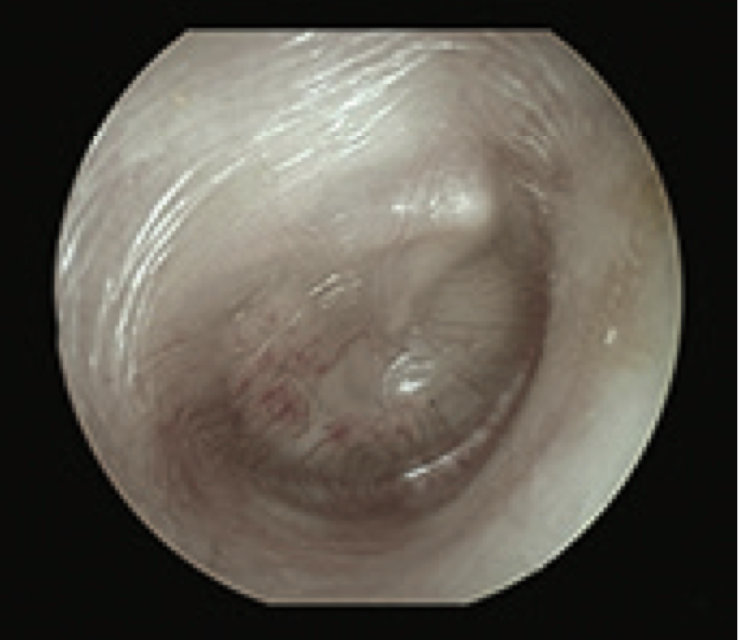

6

Q

What is this?

A

Glue Ear

- TM dull and retracted

- TM is grey